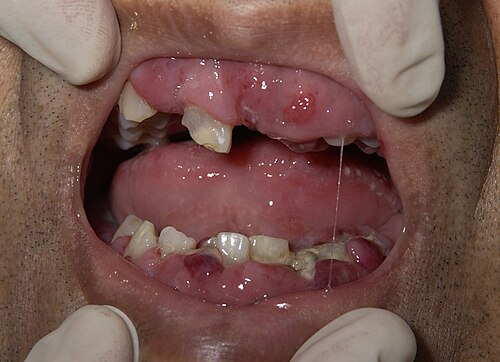

Simptomi bolesti nastaju kao posljedica zakazivanja funkcije koštane srži i/ili infiltracije određenih organa uslijed širenja bolesti. Mogu se javiti simptomi anemije koja nastaje zbog nedovoljnog stvaranja eritrocita, sklonost infekcijama zbog oslabljenog stvaranja limfocita ili povećane sklonosti krvarenju zbog nedostatka trombocita.